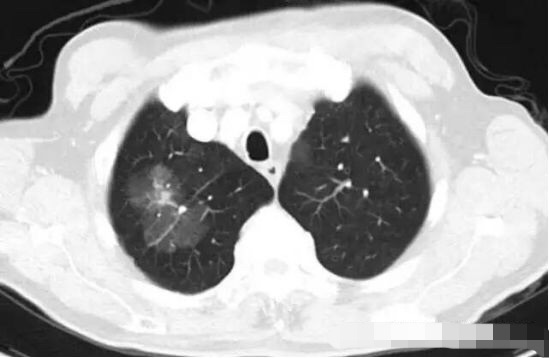

病例3

突然出现的磨玻璃结节